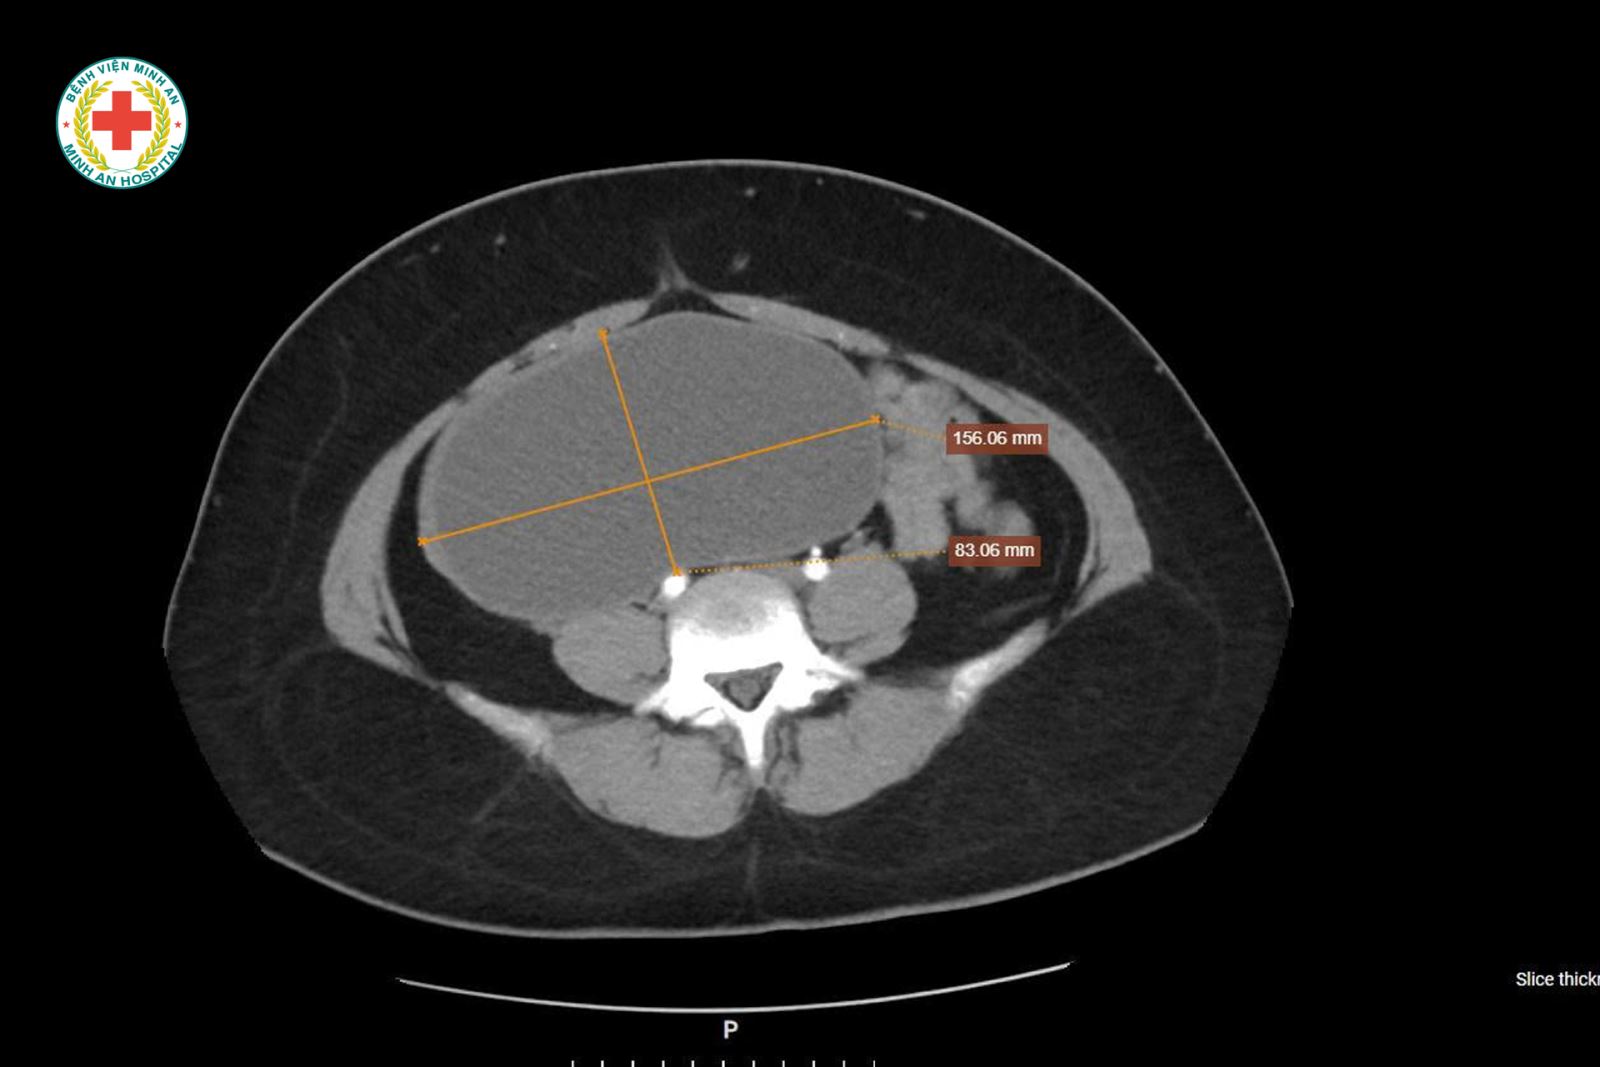

Khoa Sản – BVĐK Minh An vừa tiếp nhận tiếp nhận một trường hợp đặc biệt: U nang buồng trứng kích thước rất lớn, tương đương thai khoảng 20 tuần tuổi, người bệnh gần như không có triệu chứng rõ ràng, chỉ xuất hiện ra máu bất thường ngoài chu kỳ. Điều đáng chú ý là bênh nhân mới 22t, chưa từng sinh nở.